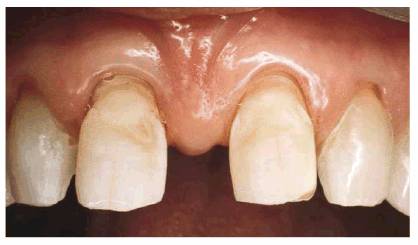

the cervical defects. Final restoration is seen in Figure 23-10D

Figure 23-10D: The final full-veneer bonding closed the diastema and restored the cervical defects.

RESULT: Figure 23-10F shows an entirely new smile with

better proportioned teeth rather than two oversized teeth. Note that the

cervical erosion on the maxillary right side has been simultaneously restored

with composite resin bonding. The mandibular anterior incisors were also

cosmetically contoured to give them a level plane of occlusion. Comparing the

before and after smiles (see Figures 23-10E

and F)

specifically illustrates how the patient's mid-upper lip naturally drops rather

low, forming a "cupid's bow." This lowered lip line tends to mask the

extra width of the central incisors, which also contributes to the illusion.

Figure 23-10E and F: Comparison of the before and after smiles shows an entirely new smile that is better proportioned by treating four anterior teeth. If only the two central incisors had been bonded, two oversized central incisors would have resulted.